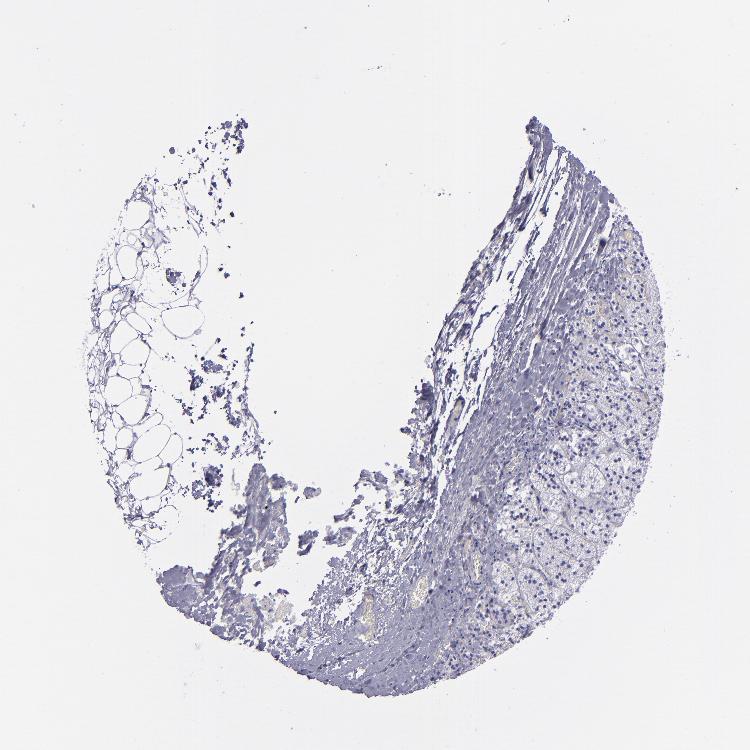

ADRENAL GLAND - Antibody stainingi

Antibody staining in the annotated cell types in the current human tissue is reported as not detected, low, medium, or high, based on conventional immunohistochemistry profiling in selected tissues. This score is based on the combination of the staining intensity and fraction of stained cells.

Each image is clickable and will lead to virtual microscopy that enables deeper exploration of all samples and also displays staining intensity scores, fraction scores and subcellular localization as well as patient and tissue information for each sample.

Antibody HPA006458Antibody HPA026773Antibody CAB002448

Glandular cells Not detectedMediumMedium